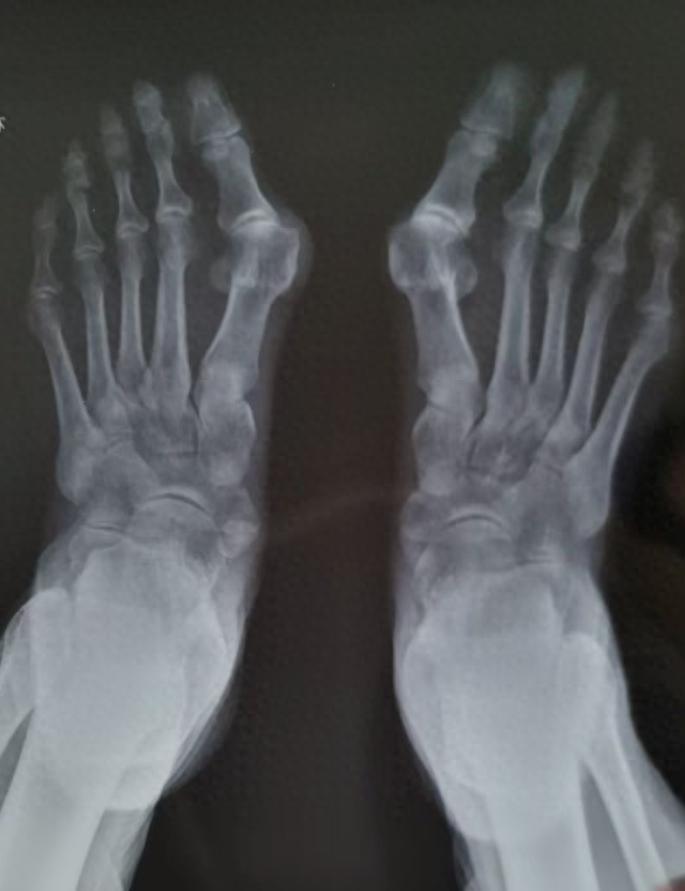

经过详细检查和评估,泰康同济(武汉)医院骨科团队为其量身定制了手术方案——采用目前较先进的微创术式,行双侧第一跖骨截骨术+骨髓内针内固定术。手术过程中,医生依次完成骨赘切除、跖骨截骨、关节复位及spear plate髓内板固定,C臂透视显示固定复位效果理想。术后检查双拇趾活动度、稳定性及关节复位情况均良好。

骨科副主任医师吴大清介绍,踇外翻俗称“大脚骨”,是引起足部不适的常见疾病之一,发病率达20%~30%左右,主要原因有遗传因素,外源性因素(如穿鞋不当等),以及外伤、风湿类疾病、痛风、神经系统疾病等。踇外翻除了不美观,还会引起脚底长老茧、疼痛、走路不稳易扭伤、易摔倒等问题。微创手术具有切口小、创伤少、恢复快、固定牢靠等优点,尤其适合对足部功能要求较高的患者。